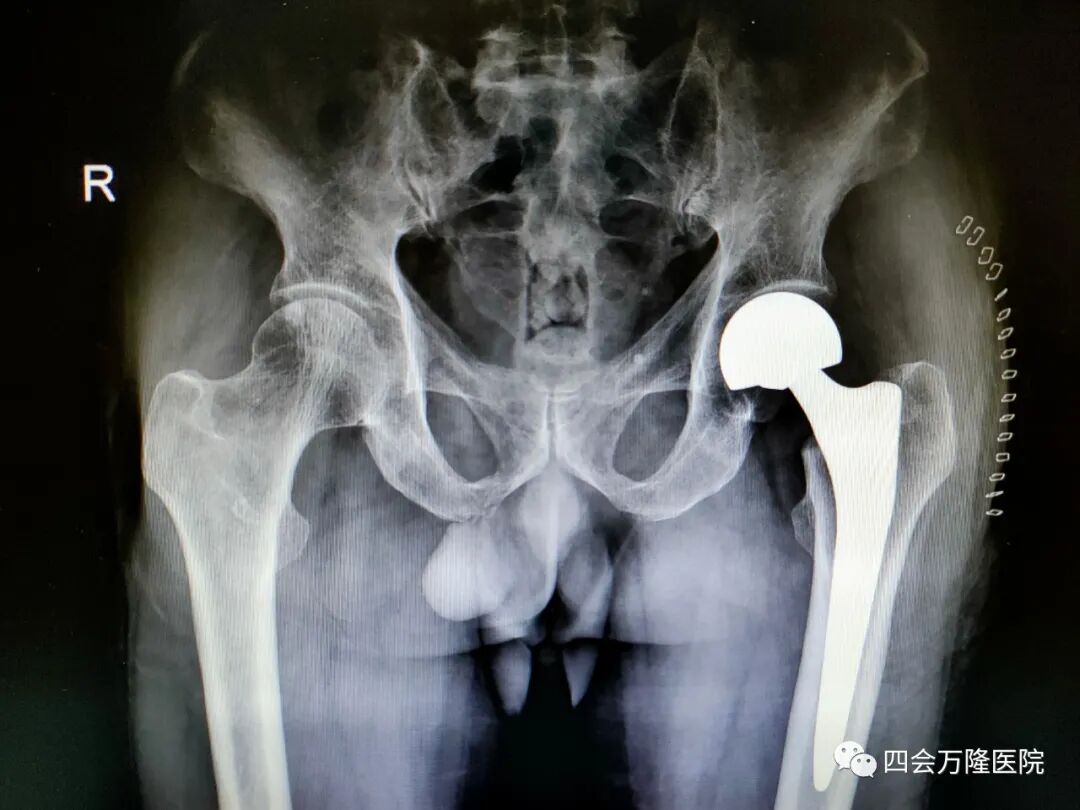

经过周密的手术计划,入院后几个小时后便安排手术,且由我院殷晓东院长亲自主刀,宋国君主任、马家剑医生协助,为李爷爷做左侧股骨头置换术。

用时仅12分钟,手术顺利完成!

(术后复查片)